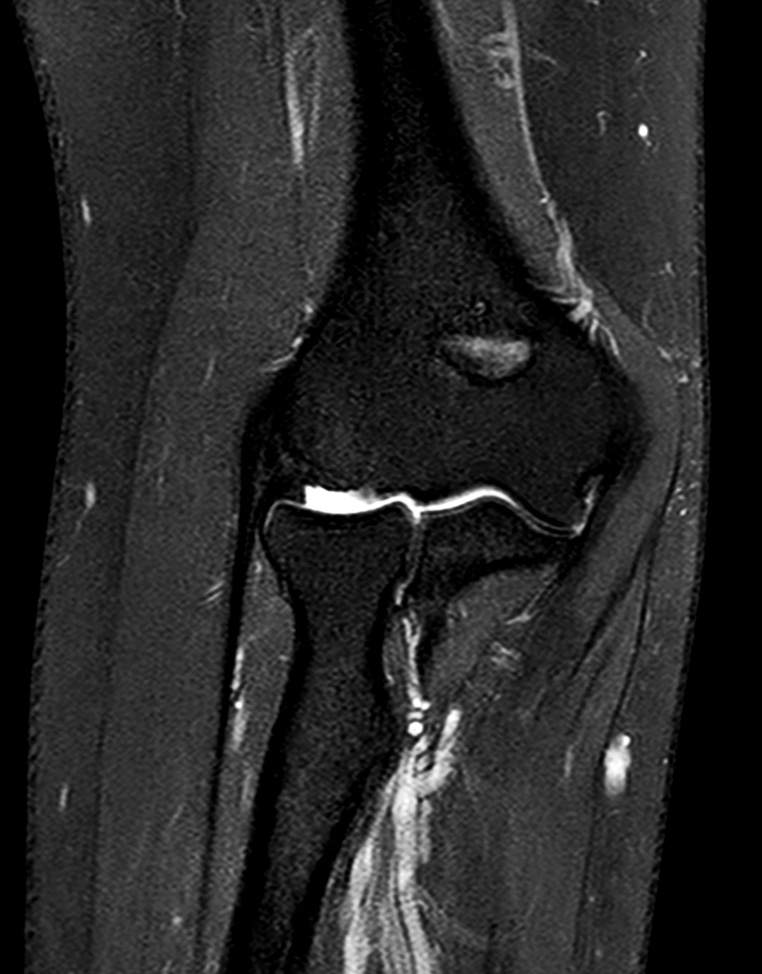

Elbow Imaging